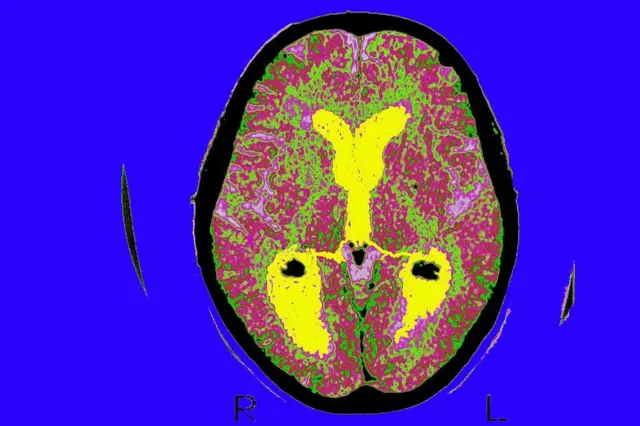

Fuente de la imagen, Getty Images